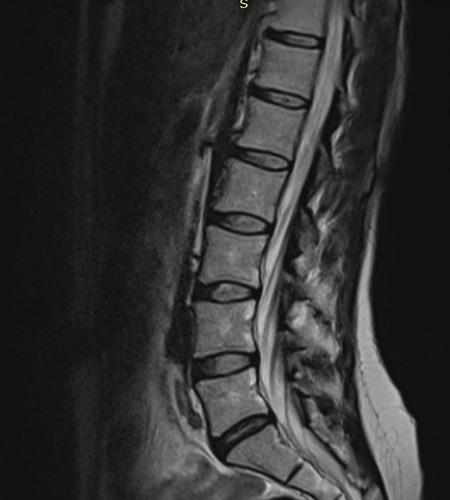

Πλήρης ακινησία, χειρουργικές επεμβάσεις και ακτινογραφίες με τη σέσουλα, ασθενείς με ταμπέλες αναπηρίας. Μήπως πρέπει να αναθεωρήσουμε την αντιμετώπιση των μυοσκελετικών πόνων;